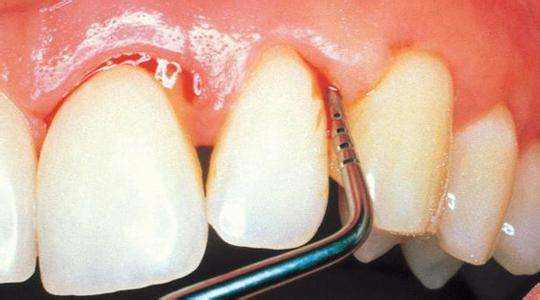

那牙周炎究竟是要怎么治疗呢?既然大多数原因都是因为清洁口腔不到位使得各种牙结石滋生,那就要先通过洁牙也就是我们通常所说的洗牙将牙结石去除干净,并刮除牙周炎内含有大量细菌毒素的病变牙骨质。